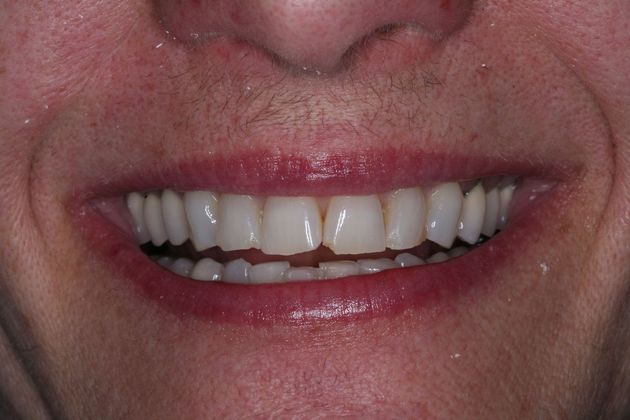

Procedures; TMJ CAT scan, TMJ deprogramming, whitening, sedation dentistry, reconstruction of all the back and upper front teeth with porcelain crowns, bite guard therapy. This foster care provider wanted to be free of the pain in her jaw joints. She had a lifelong history of grinding, many of her back teeth were breaking down and her bite was off. Her treatment was performed in sections to spread out the cost. She and her husband were so pleased with the result!